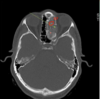

ANALISE A TOMOGRAFIA

Quando vaoms pensar em sinusite fúngica?

Quando temos, além da destruição do osso, presença de calcificações dentro da opacidade